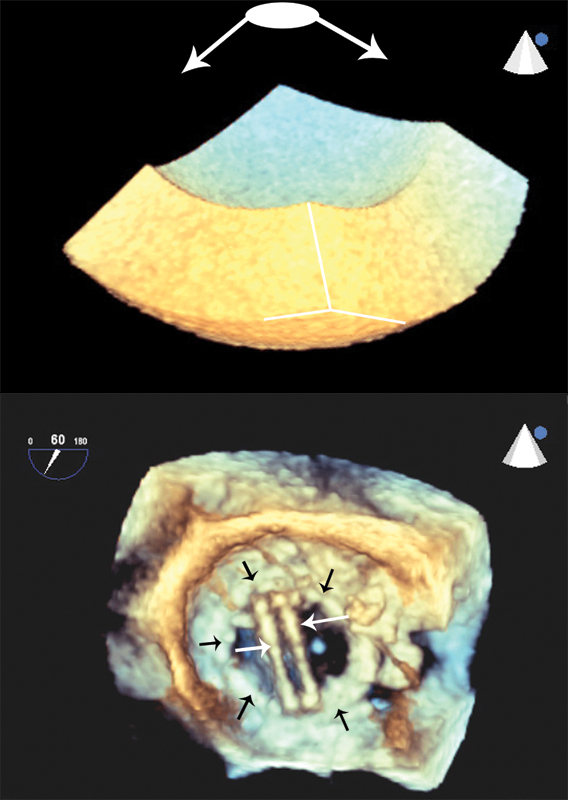

فحوصات تشخيصية لبعض امراض القلب والشرايين التاجية